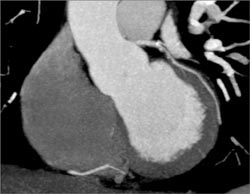

Calcified Plaque in LAD